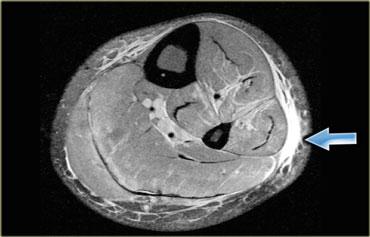

Cơ phụ (Accessory muscles)

Cơ phụ có thể biểu hiện như một khối không triệu chứng, không đau, hoặc kèm theo các triệu chứng chèn ép thần kinh hay chèn ép mạch máu.

Hình bên trái minh họa một trường hợp cơ dép phụ ở mặt trong cổ chân, gây chèn ép thần kinh chày (tức hội chứng ống cổ chân).

Để chẩn đoán được thực thể này, người đọc cần phải thực sự thành thạo về giải phẫu của vùng đang khảo sát.

Hình bên trái minh họa một loại cơ phụ thường gặp: cơ dép phụ.

Thông thường, cơ dép bám gần như hoàn toàn vào gân Achilles, với một gân dép nhỏ đi phía trước gân Achilles.

Tuy nhiên, ở khoảng 1-2% dân số, cơ dép đi xuống và bám trực tiếp vào xương gót.

Tình trạng này biểu hiện như một khối có thể sờ thấy và thường, nhưng không phải lúc nào cũng, xuất hiện hai bên.

Hình bên trái cho thấy một cơ dép ở vị trí thấp, nhưng không có điểm bám gân riêng biệt vào xương gót.

Hình bên trái là một ví dụ khác về cơ phụ nằm ở phía trong so với cơ gấp ngón cái dài (ở giữa) và cơ mác ngắn (ở ngoài).

Đây là vị trí thường gặp của các cơ phụ, và có nhiều loại cơ khác nhau có thể xuất hiện tại đây (để phân biệt cần xác định vị trí bám của gân).

Lý do bệnh nhân được chỉ định chẩn đoán hình ảnh là vì cơ phụ này chèn ép bó mạch thần kinh lân cận, dẫn đến teo cơ bàn chân hoặc hội chứng ống cổ chân với cảm giác tê bì lòng bàn chân hay yếu cơ.